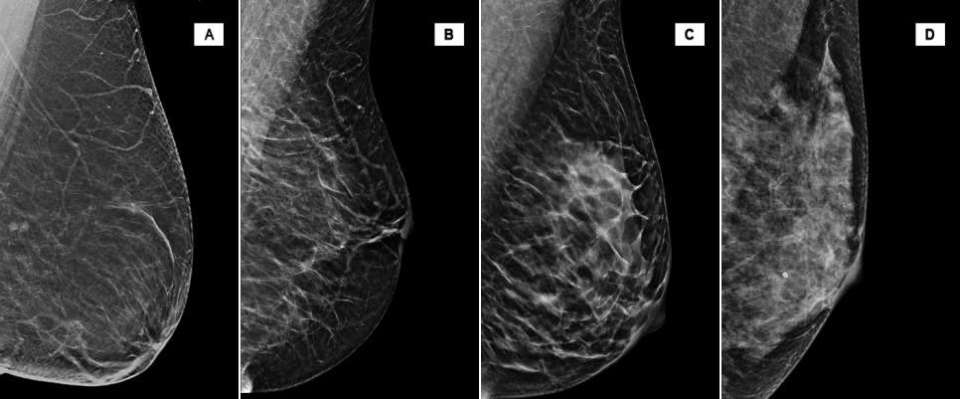

Breast density, or mammographic density, is a ratio of the proportion of fibroglandular tissue relative to fat in the breast. The current fifth edition of American College of Radiology Breast Imaging Reporting and Data System (BI-RADS) lexicon classifies breast density in four categories [2].

Current literature reports the proportion of the screening population in each category as 10% in Category A, 40% in Category B, 40% in Category C, and 10% in Category D. Therefore, approximately 50% of screening population has dense breast tissue, as defined by BI-RADS [1].